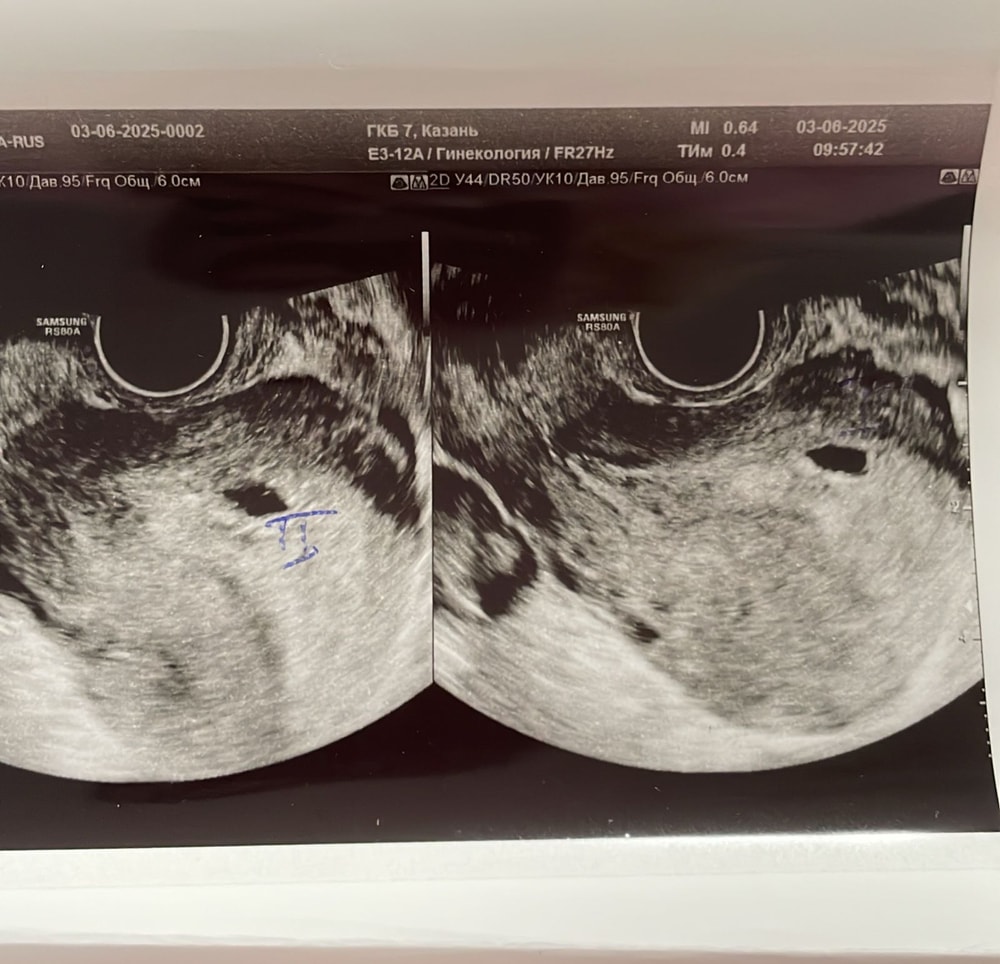

Ксения , врач про гематому ничего не говорила,есть киста большая,но это не она.вот киста 58мм Изображение